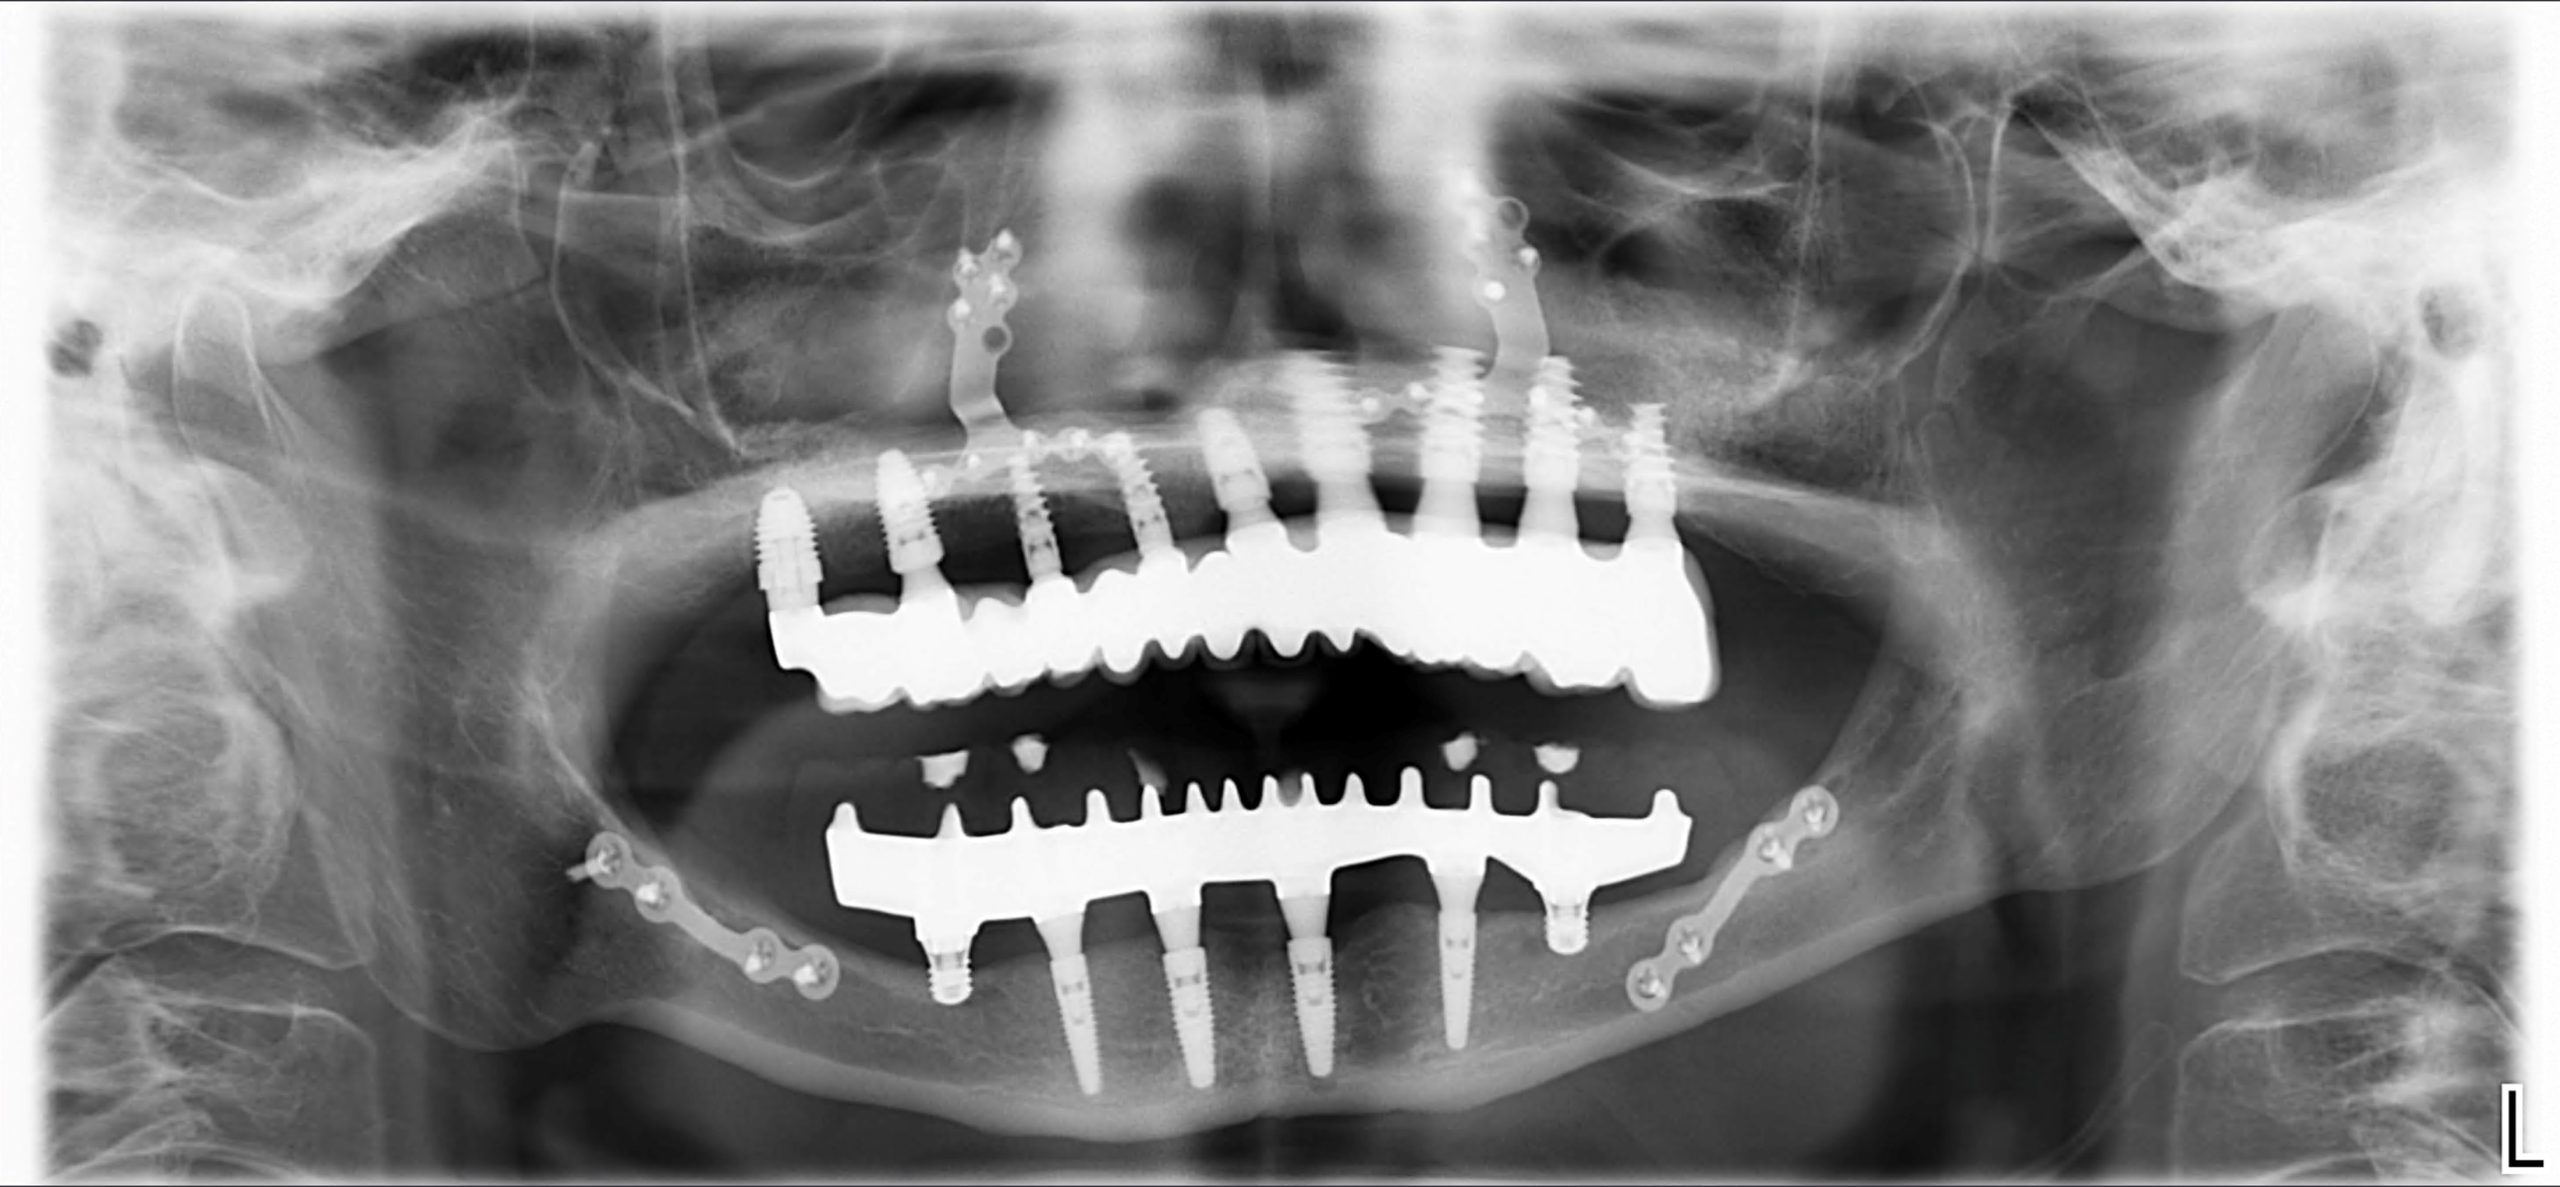

Primero realizamos un estudio con radiografía 3D (CBCT) y modelos digitales para medir la cantidad, forma y calidad del hueso mediante criterio medico e inteligencia artificial. Con esta información decidimos la mejor opción de implante dental. La elección depende de la seguridad, las expectativas del paciente y las altas tasas de éxito de cada técnica. Estas soluciones permiten colocar dientes fijos casi de inmediato incluso en pacientes con mucho hueso perdido.

Antes de la cirugía, planificamos todo en 3D: elegimos el tamaño, la trayectoria y la posición exacta de los implantes. Usamos guías quirúrgicas personalizadas que aumentan la precisión y protegen las estructuras anatómicas cercanas.